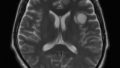

簡単に自分の病気の説明をしておくと、グリオーマ(【備忘録】グリオーマ・びまん性星細胞腫:神経膠腫)という脳の実の部分にできる悪性腫瘍です。グレード1~4で悪性度を表すのですが、グレード2の判定です。

非常に幸運なことに無症状の段階で発見できたので、悪性度はまだ低くてサイズも小さいです。それでもピンポン球くらいあります。

腫瘍が言語中枢の近くにありデリケートな手術となりますので、地元の病院で紹介してもらった大学病院で手術します。